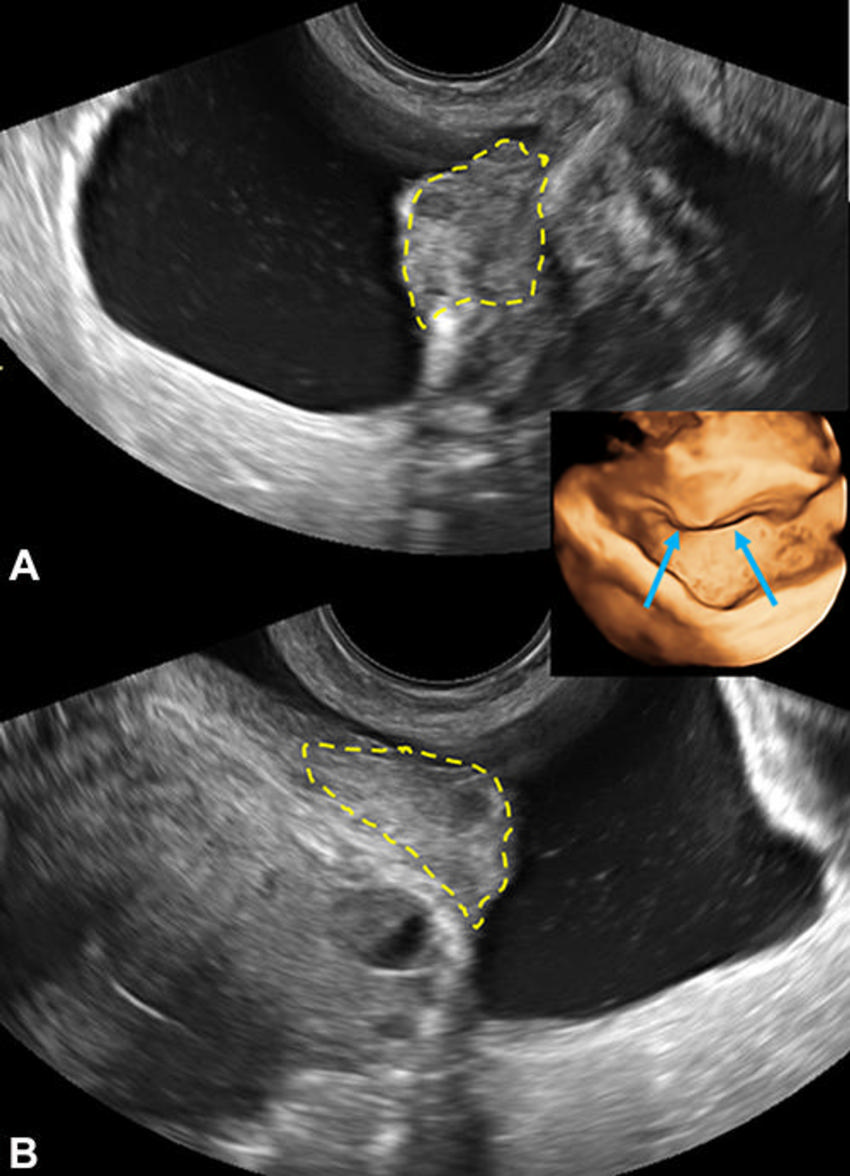

Figure 11. Transvaginal US images of bladder endometriosis in a 31-year-old patient with dysuria shows a midechogenicity nodule (yellow outline) extending from vesicouterine space into the detrusor muscle, longitudinal (A) and transverse (B) . Three-dimensional US virtual cystoscopic view is shown (inset, arrows). This is a category A (direct endometriosis) observation.